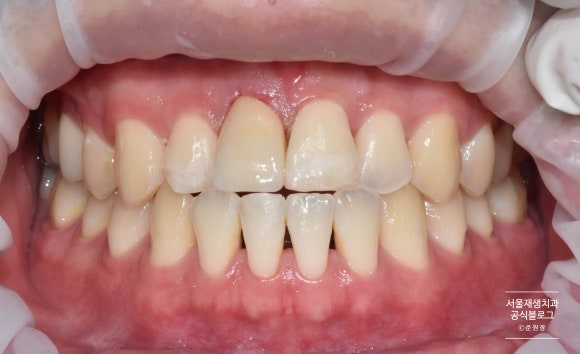

크라운 부착과 심미레진수복

짠! 자연치아보다 더 매끈하고 반짝거리는 크라운이 도착했습니다.

어떤 것이 자연치아였는지 제가 봐도 헷갈리네요^^

파절되어 있던 양 옆 치아와 아래치아도 레진을 이용하여 당일에 심미수복을 진행하였습니다.

치료 전 후 비교

치료 전 후 사진입니다.

꼬박 3주가 걸린 과정이었습니다.